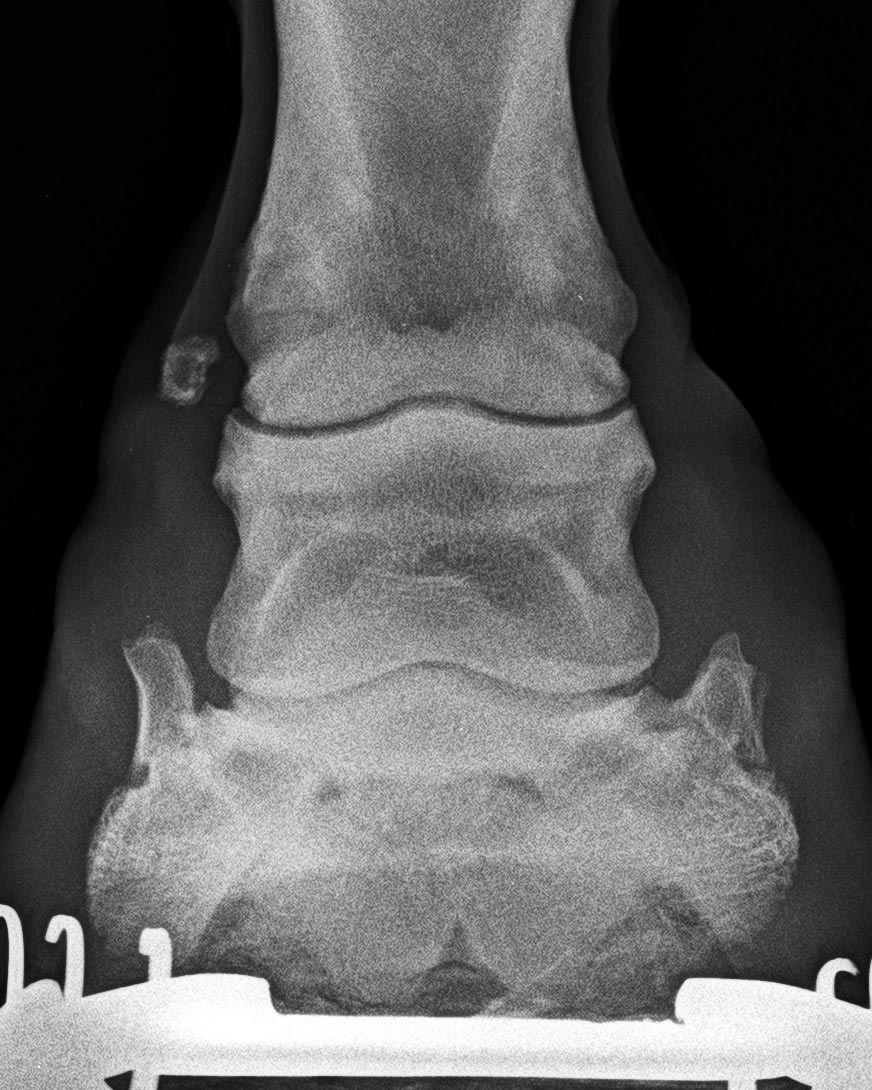

Höchstgradige Krongelenksarthrose mit isolierter Verknöcherung innen (wie auf folgender Aufnahme)